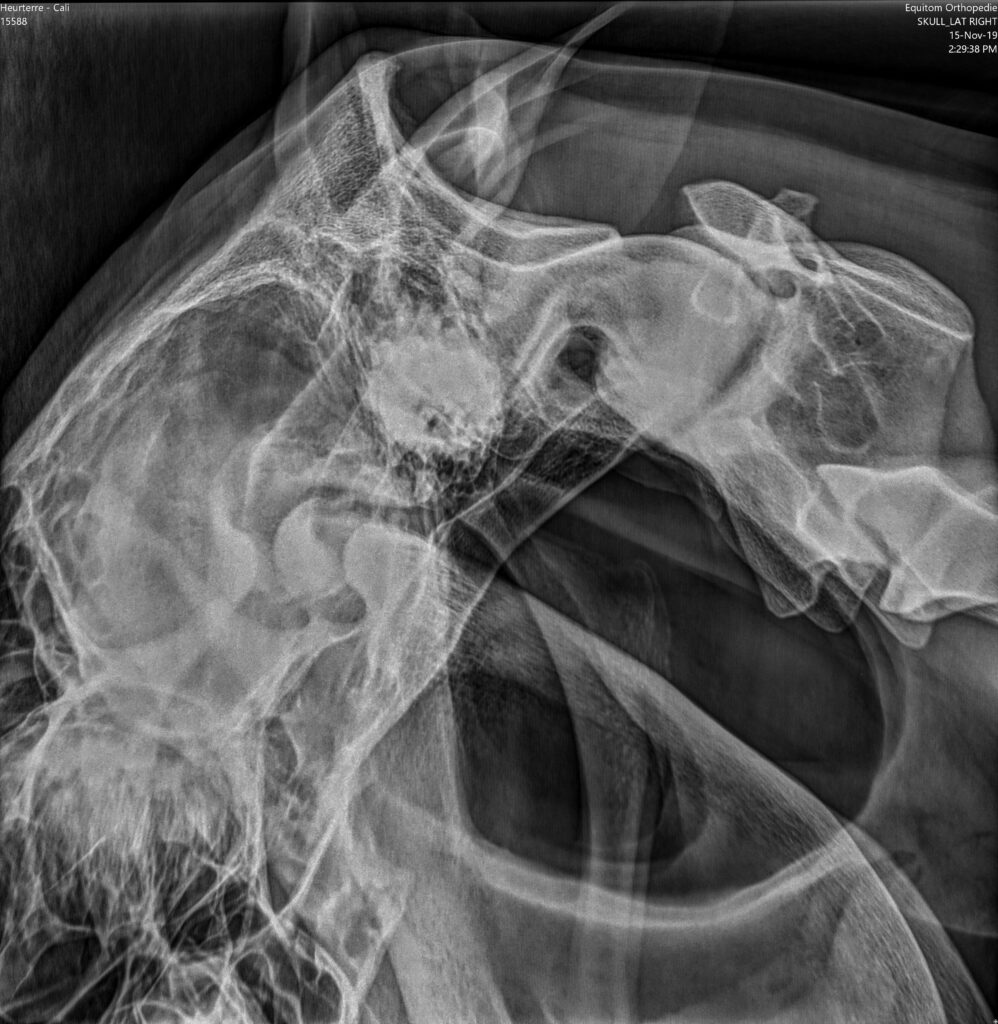

Každý kůň má dva vzdušné vaky, které leží po stranách hrdla. Jsou to pytlovité výchlipky Eustachovy trubice, která propojuje hrdlo a ucho koně. Vaky jsou naplněny vzduchem a jsou jasně viditelné na rentgenových snímcích jako tmavé plochy (obr. 1). Jejich funkce stále není zcela objasněná, ale je jisté, že kolem nich nebo přímo skrz ně vedou velmi důležité struktury.